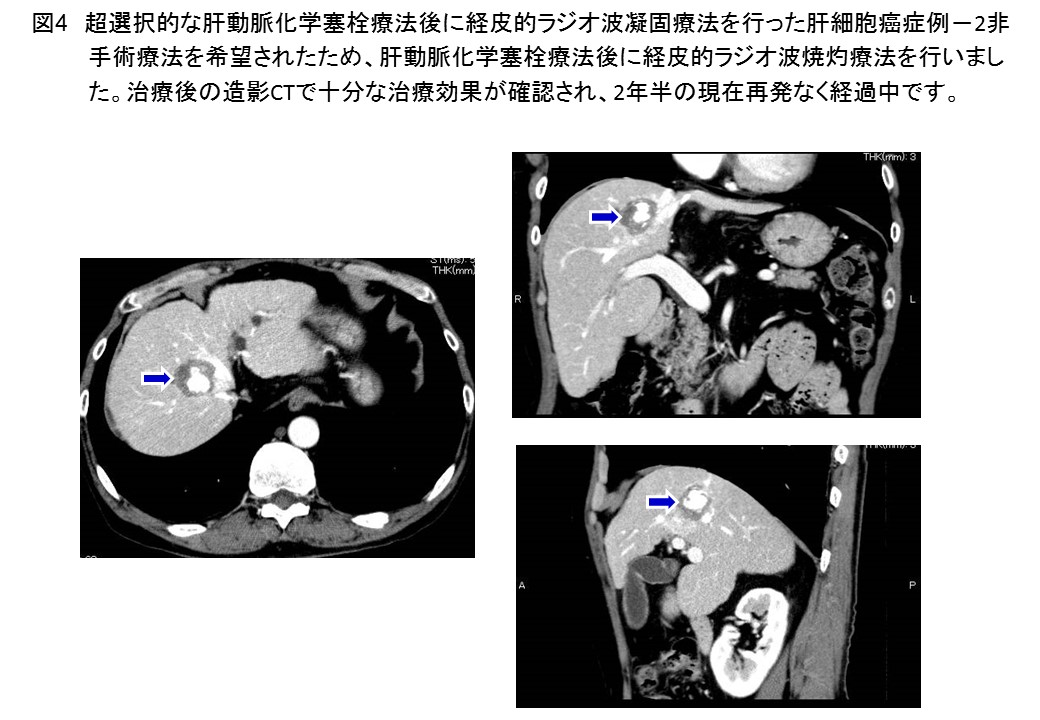

肝細胞癌に対する肝切除、局所焼灼療法、肝動脈・門脈塞栓療法、薬物療法のすべてに対応可能です。血管造影下治療や薬物治療については別項を参照ください。肝移植や放射線治療は熊本大学附属病院と連携して行っています。局所焼灼療法は経皮的な手技ばかりでなく、腹腔鏡や胸腔鏡による治療が可能なことが特徴です(図2)。超選択的な肝動脈化学塞栓療法後に経皮的ラジオ波焼灼療法を行った高悪性度肝細胞癌症例(図3, 4)を提示します。効果判定は、造影エコーや造影CTによる3次元画像により確実に行います。最近、肝動脈門脈短絡を伴う巨大肝細胞癌に対する肝動脈化学塞栓療法とレンバチニブによる分子標的治療後のコンバージョン肝切除症例を経験し、報告しました (Sato N, Beppu T, et al. Anticancer Res 2019) (図5-10)。肝切除後に100万を超える腫瘍マーカー (AFP)は正常化しました。C型肝炎の治療も終了し、治療開始後7年間再発なく元気にされています。このような肝癌の薬物療法施行例も年々増加しています(図11)。